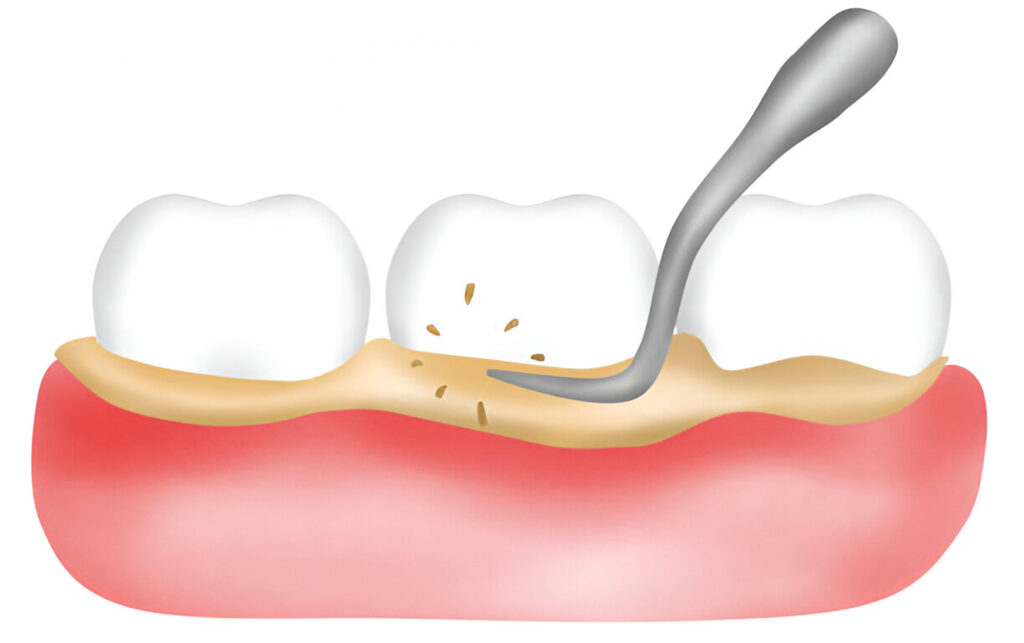

Scaling & Root Planing

A deep-cleaning procedure that allows for plaque and tartar that sit under the gum line to be cleansed and help in healing.

Root Surface Debridement

Helping combat advanced gum diseases is root surface debridement, an advanced cleaning procedure that aids in removing bacteria and plaque sitting on the root of the tooth.

What Is Root Surface Debridement?

Root surface debridement is an advanced dental cleaning procedure that targets bacteria and plaque buildup on the root of the tooth, helping to combat gum disease and restore oral health.